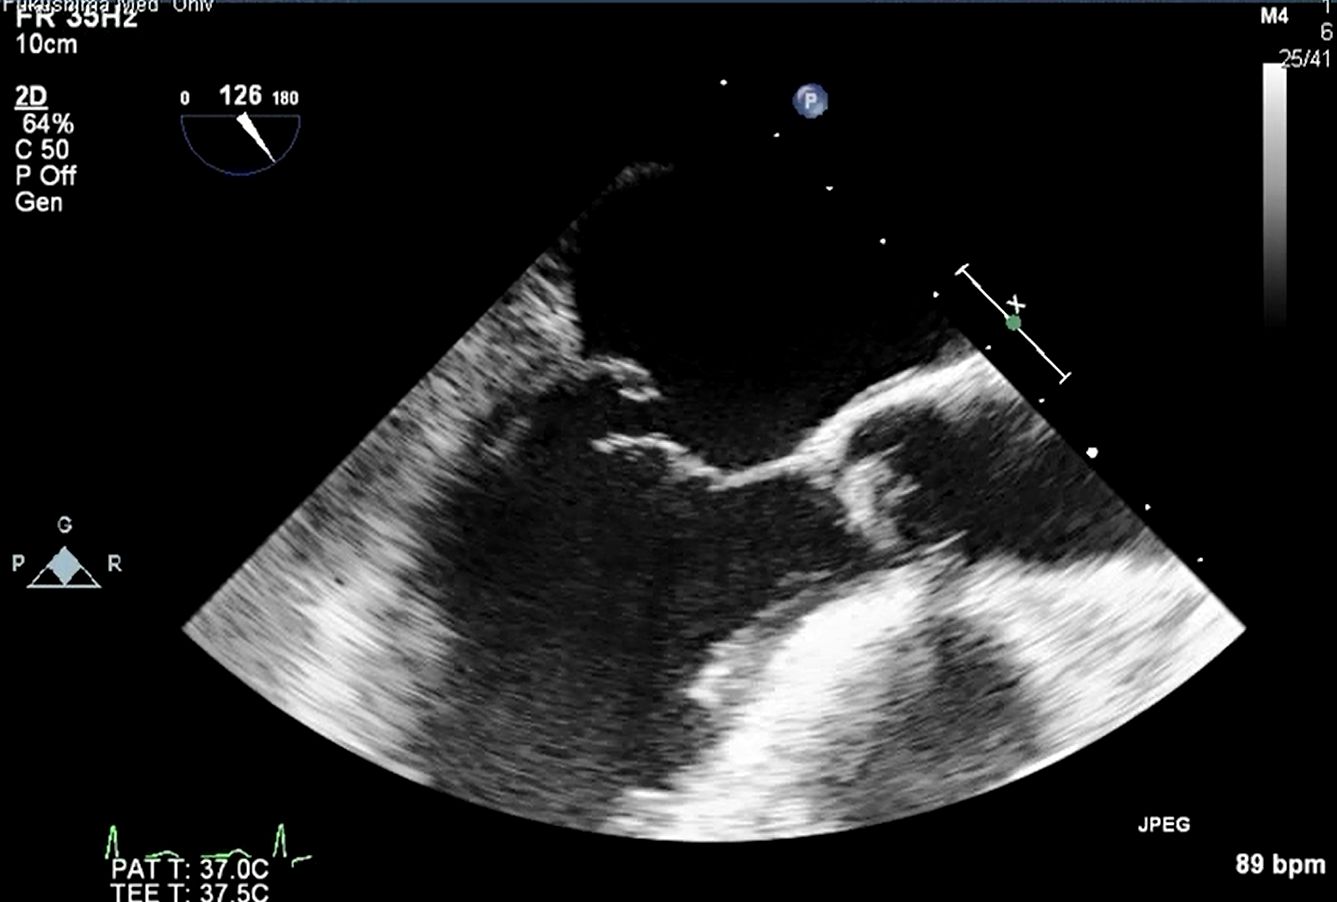

3D心エコー:どうやって使えば手術に役立てられるか? 解剖学的。循環器内科医のための経食道心エコー〜基本的な手技から術中・術。figure4.image1.png。ご覧いただきありがとうございます。「経食道心エコー II」の出品です。- タイトル: 経食道心エコー II- 監修者: 野村実- 編集者: 国沢卓之- 定価: 12,500円+税【状態について】以下、コンディションの詳細です。写真も併せてご確認ください。■カバーの状態:【 良 】目立つ傷や汚れなし■表紙・裏表紙の状態:【 良 】比較的綺麗■ページの状態:【 良 】書き込み・マーカー・目立つ汚れなし【ご購入について】・即購入OKです。・中古品であることをご理解の上、ご購入をお願いいたします。・ご不明な点は、お気軽にコメントください。【発送について】・梱包:OPP袋で防水対策をし、封筒に入れて発送します。・発送方法:佐川急便/日本郵便(ネコポス)を予定しています。匿名配送です。・発送までの日数:通常、ご購入(お支払い確認後)から1~2日以内に発送いたします。丁寧な検品と梱包を心がけております。よろしくお願いいたします。#経食道心エコー#TEE#循環器#心臓血管外科#医学書。循環器内科医のための経食道心エコー〜基本的な手技から術中・術。矯正歯科治療におけるスマイルデザインと審美処置。裁断済 在宅医療 藤田総診リアル実践ガイド たんぽぽ先生の在宅報酬算定マニュアル。インナービューティーダイエット プレミアム レシピ。口腔病理アトラス 第三版。救急救命スタッフのためのITLS。視能訓練士 国家試験問題集 第43〜48回 2019年発行。心電図検定参考書。【裁断済み】四肢切断術のすべて。麻酔科プラクティス 周術期呼吸管理。臨床検査技師 ポケットマスター。絵でみる和漢診療学。CBT・医師国家試験のための レビューブック 産婦人科 2022-2023